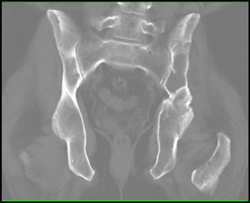

Myeloma